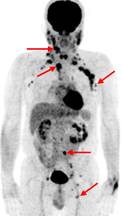

Ca lâm sàng 2: Bệnh nhân Nguyễn T.V., nữ, 72 tuổi. Chẩn đoán: U lympho ác tính không Hodgkin biểu hiện tại phổi, GPB: WF6. Hình CT và PET/CT cho thấy khối u phổi trái tăng hấp thu FDG (vòng tròn) với max SUV=7,94.

Ca lâm sàng 3: Bệnh nhân Nguyễn X.T., nam, 58 tuổi. Chẩn đoán: U lympho ác tính không Hodgkin, GPB: WF6. Hình PET cho thấy tổn thương ở phổi, hạch, xương, tuyến thượng thận hai bên (mũi tên). Hình CT và PET/CT cho thấy tổn thương tăng hấp thu FDG tại vị trí tuyến thượng thận hai bên (mũi tên).